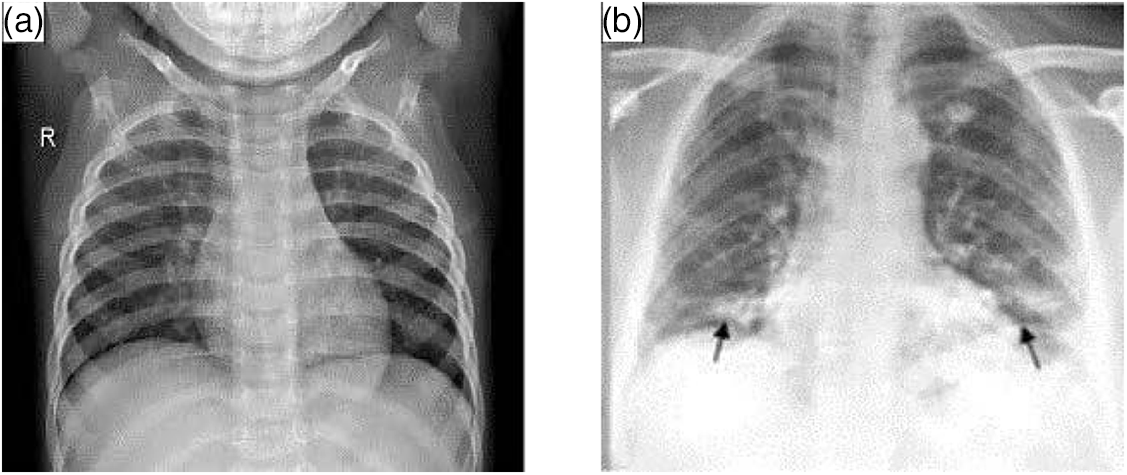

X-ray CXR images are more common in chest image detection than CT scanning tomography because they are simpler to collect. The primary barrier to using CXR in the imaging diagnosis of COVID-19 is the absence of information that can be verified visually. As illustrated in Fig. 2, CXR pictures reveal airspace turbidity, which is mostly dispersed in the lung margins [22]. In practice, CXR and CT are frequently combined to provide a more accurate diagnostic evaluation [23].

Figure 2: Lungs images of X-ray. (a) Normal (b) with COVID-19

Table 2 displays the outcomes of the examination of texture features. The textural properties of the CXR images of healthy lungs vary from those of COVID-19-infected lungs. However, some variations are less visible than others. The contrast of infected photos is two to three times greater than that of healthy lung images.